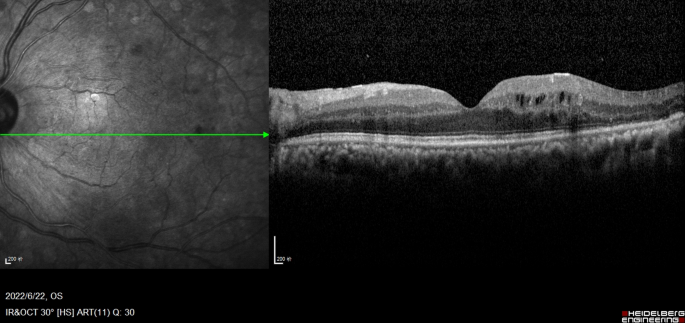

OCT images were acquired using 6-mm vertical and horizontal scans centered on the fovea in high-resolution mode with spectral domain OCT (SD-OCT, Heidelberg Spectralis OCT, Heidelberg Engineering, Germany). Recorded quantitative variables included (1) central macular thickness (CMT) and (2) the total number of hyperreflective foci (HRF) across retinal layers. Qualitative parameters were assessed for (1) size of intraretinal cysts (IRC), (2) integrity of the ELM and EZ, (3) presence of disorganization of the inner retinal layers (DRIL), and (4) presence of subfoveal fluid (SRF). All the subjects underwent examinations twice. All OCT images were analysed by the blinded retina specialist(Li-na Lv) and averages were determined. According to the TCED-HFV grading system (Table 1), the DME was divided into early, advanced, severe, and atrophic stages10 (Table 2, represented in Figs. 1, 2, 3 and 4).

Early DME Multiple perifoveal cystoid spaces in the INL, the OPL, with mild thickening of the temporal area of foveal, absence of any visible adhesion or traction between vitreous cortex and retina, hyperreflective foci are less than 30 in number. The TCED-HFV grading is T = 1, C = 2, E = 0, D = 0, H = 0, F = 0, and V = 0.